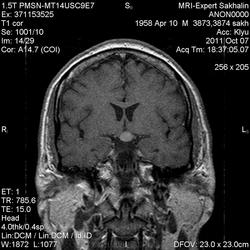

Аденома гипофиза

Вот такая аденома гипофиза сегодня.Мужчина с жалобами на снижение зрения.